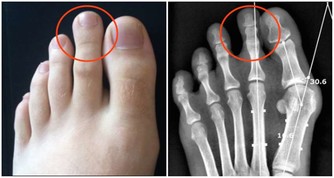

於是我繼續追問一些平日裡的一些症狀,才得知患者平時總是出現腰酸,怕冷,容易疲倦,不思飲食,吃完就會感覺腹脹發悶,而患者之前一直大意以為是自己體力不支,總是吃外賣所導致。曾多次行結腸鏡檢查,診斷為慢性直腸炎。